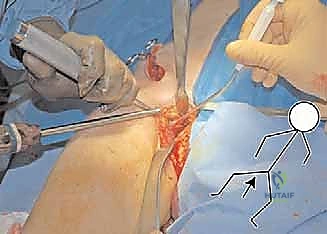

2. الشقوق الجراحية (Incisions)

يُجري الدكتور هطيف شقوقاً استراتيجية مصممة لتقليل الضرر العضلي وترك ندبات تجميلية صغيرة قدر الإمكان. يتم الوصول إلى العظام الثلاثة بعناية فائقة وتجنيب الأوعية الدموية الحساسة.

هنا تكمن عبقرية الإجراء. يتم استخدام مناشير جراحية دقيقة لعمل قطوع في:

* عظم الإسك (Ischium): العظم السفلي الخلفي للحوض.

* عظم العانة (Pubis): العظم الأمامي للحوض.

* عظم الحرقفة (Ilium): العظم العلوي العريض للحوض.

بمجرد اكتمال هذه القطوع الثلاثة، يصبح التجويف الحقي (الكوب) منفصلاً تماماً عن بقية الحوض، مع بقاء إمداداته الدموية سليمة.